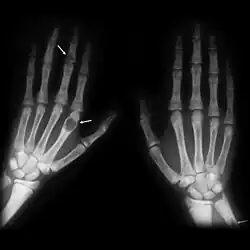

| Brown tumours of the hands in a patient with hyperparathyroidism. |

The brown tumor is a bone lesion that arises in settings of excess osteoclast activity, such as hyperparathyroidism. They are a form of osteitis fibrosa cystica. It is not a neoplasm, but rather simply a mass. It most commonly affects the maxilla and mandible, though any bone may be affected.[1] Brown tumours are radiolucent on x-ray.

Radiographically, brown tumor may show no detectable changes or a generalized osteoporosis. Partial loss of lamina dura around the teeth may occur but is not a constant feature. Focal Lesions (Brown Tumor) present as sharply defined, round or oval radiolucent areas which may appear multilocular. Such lesions occur more frequently in mandible than maxilla [6]